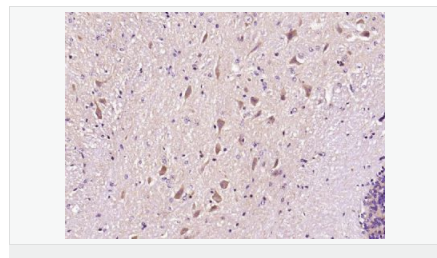

Synuclein 包括α-Synuclein,β-Synuclein 和γ-Synuclein 是神經(jīng)細(xì)胞中富含的前突觸蛋白。α-Synuclein,Alzheimer’(AD)病淀粉樣蛋白沉積的成份之一,集中分布在神經(jīng)細(xì)胞的包體和突觸。在帕金森病人中發(fā)現(xiàn)有α-Synuclein的變異型,而γ-Synuclein與軸突病理學(xué)有關(guān)。此抗體將為Lewy小體癡呆癥、Parkinson癥、AD和其它一些神經(jīng)性疾病提供有用的病理診斷。